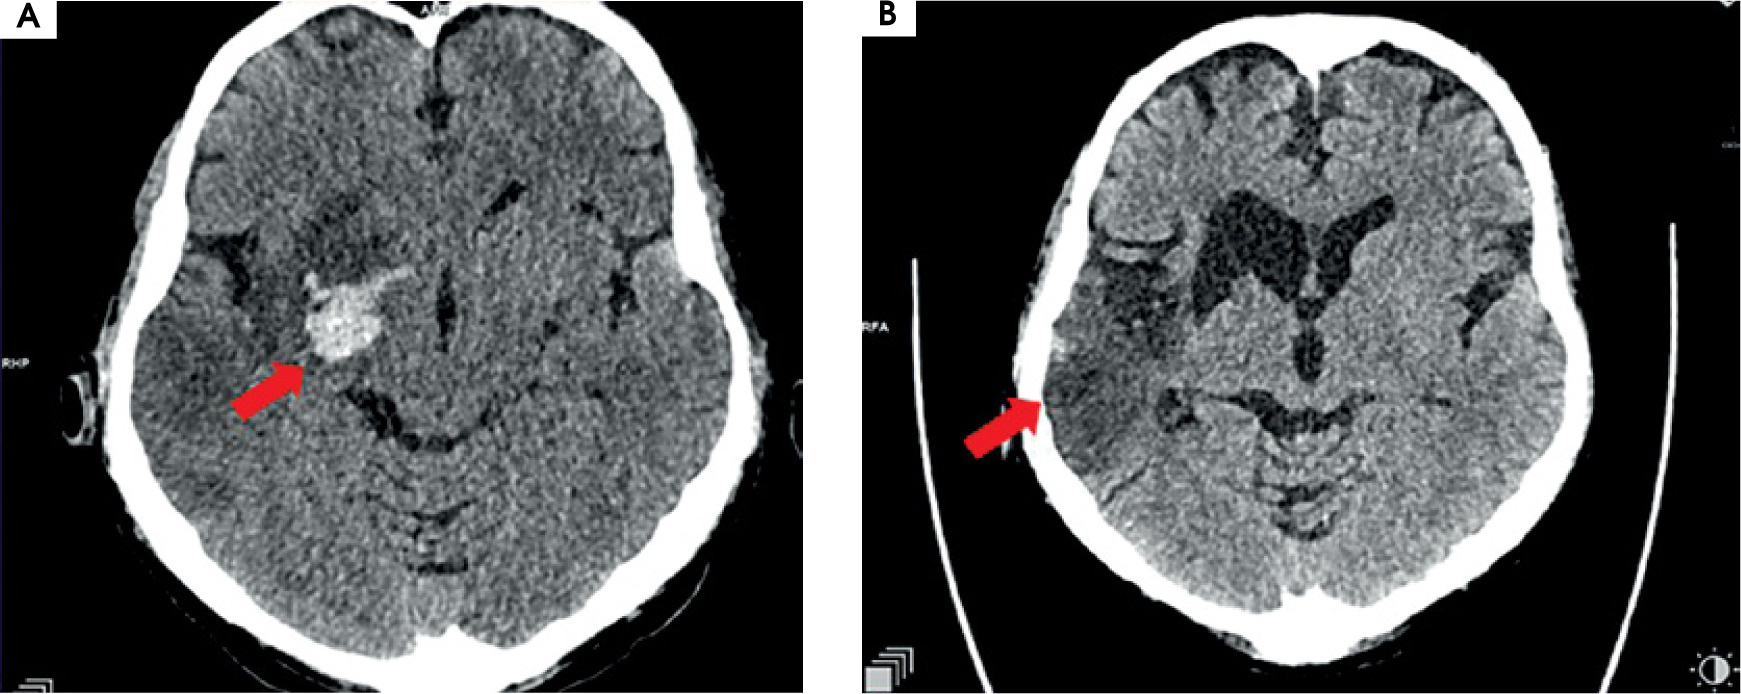

After MT the blood flow in the artery was returned with TICI 3 (Figure II). The day after the MT, control CT showed haemorrhagic foci (Figure III). The patient returned to the ICCU three days later. His neurological status was the same as before the MT of RMCA. In repeated CTs of the brain, haemorrhagic foci were still present (Figure IVA). In the following days of hospitalization, the resolution of haemorrhagic and evolution of ischemic cerebral lesions were observed (Figure IVB).

Figure III

Scans from control computed tomography of the brain performed the day after the procedure of thrombectomy. A) On the right side of the brain, in deep structures, hyperdense haemorrhagic foci are seen, with the greatest one 20 × 21 × 15 mm and a smaller satellite. B) Surrounding the M1/M2 segment of right middle cerebral artery, probably minor subarchnoid haemorrhage in the lateral sulcus on the right side is present. C) Acute ischemic lesions located cortico-subcortically in the right hemisphere, including part of the frontal, occipital, and temporal lobe and also thalamus, the islet, caudate nucleus, mass effect is present as a narrowed frontal horn of the right ventricle and a narrowed sulcus above the area of stroke